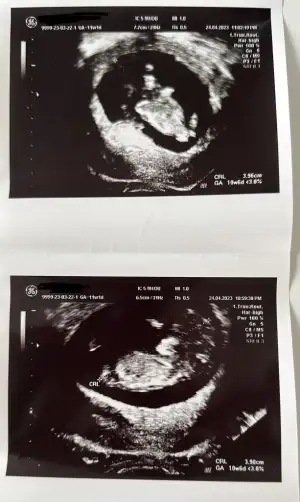

Kaç haftalıktın canım Ramzi için büyümüş artık ama nubu da belli değil. Ama kız hissettim.

8+6 kuzum kaçırdık vakti deseneKaç haftalıktın canım Ramzi için büyümüş artık ama nubu da belli değil. Ama kız hissettim.

10-11. Haftalarda çıkıyor nub yani çıkıntı8+6 kuzum kaçırdık vakti desenenubu nasıl belli olması lazım

Merhaba bana da tahmin yapabilir misinizKaç haftalıktın canım Ramzi için büyümüş artık ama nubu da belli değil. Ama kız hissettim.

Merhaba bana da tahmin yapabilir misiniz

Pozisyonundan dolayı anlayamadım doktor bi tahmin yaptı mıTahmin alabilir miyim

Şansımıza artık10-11. Haftalarda çıkıyor nub yani çıkıntıkızlarda düz erkeklerde daha dik açılı oluyor o çıkıntı

12 haftaymis dr tahminde bulunmadi mi bana erkek gibi geldiTahmin alabilir miyim